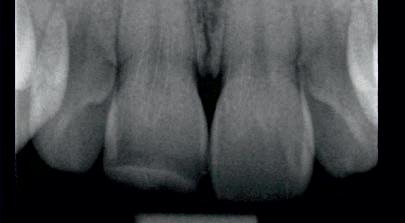

On clinical examination, UR1 was responsive to viability testing, and did not present periapical lesions on the radiograph performed on the same day (Figure 1). UR1 was discoloured and in a more palatal position than the contralateral central UL1 (Figure 2). The aesthetic analysis highlighted an asymmetry of the gingival zenith between UR1 and UL1. Through the use of a periodontal probe, after plexus anaesthesia, the altered passive eruption of the type IA junctional epithelium was confirmed according to the classification of Coslet et al. (Figure 3).

FIGURE 1: Radiograph without periapical lesion.